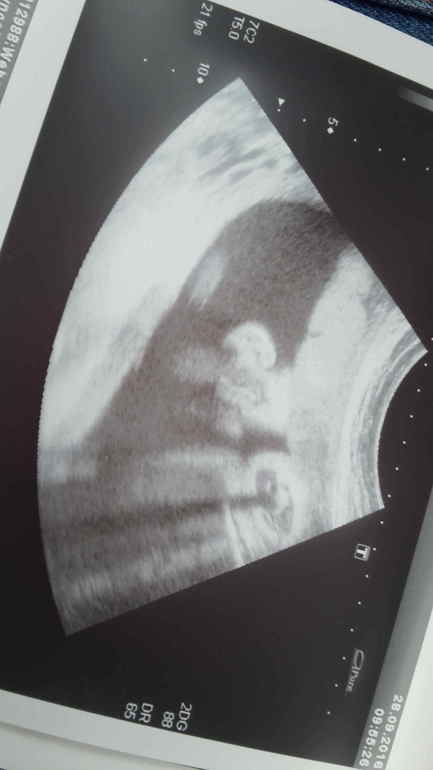

ну и о самом ВАЖНОМ..это УЗИ)))) ОН такой уже хорошенький большой и губки пухленькие и щёчки и носик картошкой))))ой не могу... обожаю его..хороший мальчишка ....спокойный никаких проблем мамочке от самого зачатия

также нам провели сразу доплер...пуповинка и сосуды матки в полной норме,вот только вес и рост я спросить забыла заболталась с доктором и забыла((( и писюн глянуть для убедительности тоже забыла,вот даю а....Ну в принципе это не важно всё отлично что ещё нужно правда?!))))